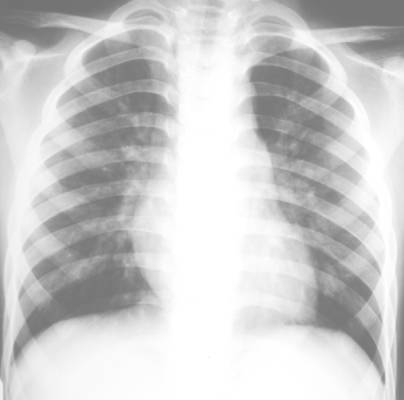

照片名称:正常胸片